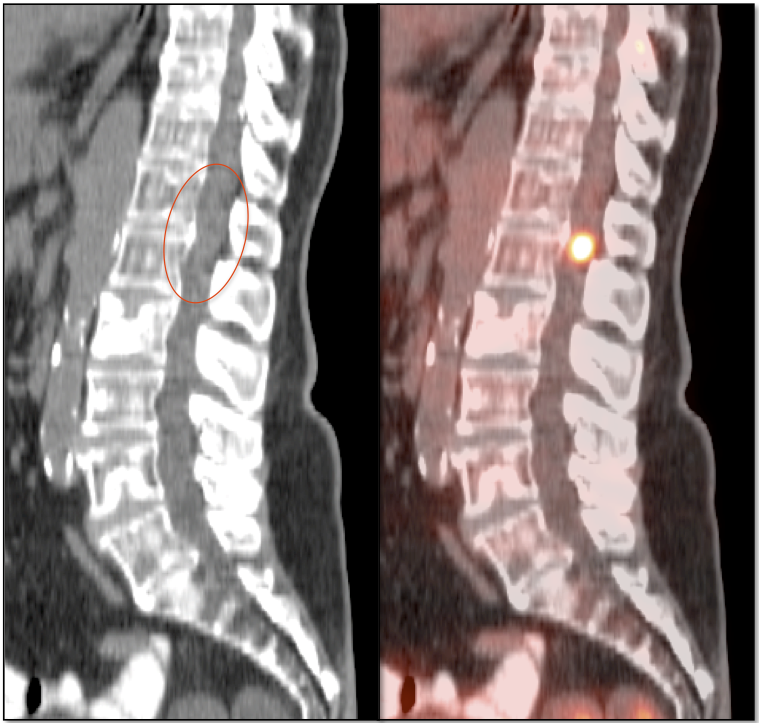

SPINAL CORD:

- Primary lesions are rarely evaluated with PET/CT.

- Metastatic lesions are not uncommon, appearing very focal, with uptake > liver activity.